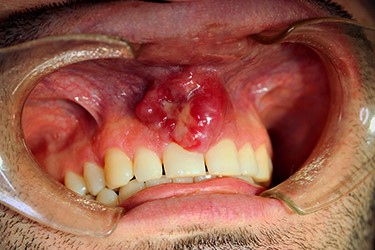

On examination, a lobulated, firm mass was seen extruding from the anterior maxillary vestibule (Fig. 1). All maxillary teeth were painless to percussion, and normal tooth mobility was present. No cervical lymphadenopathy was detected, nor any changes with cranial nerve examination. A maxillofacial computerized tomographic (CT) scan revealed an osteolytic lesion on the maxillary alveolar process (Fig. 2).